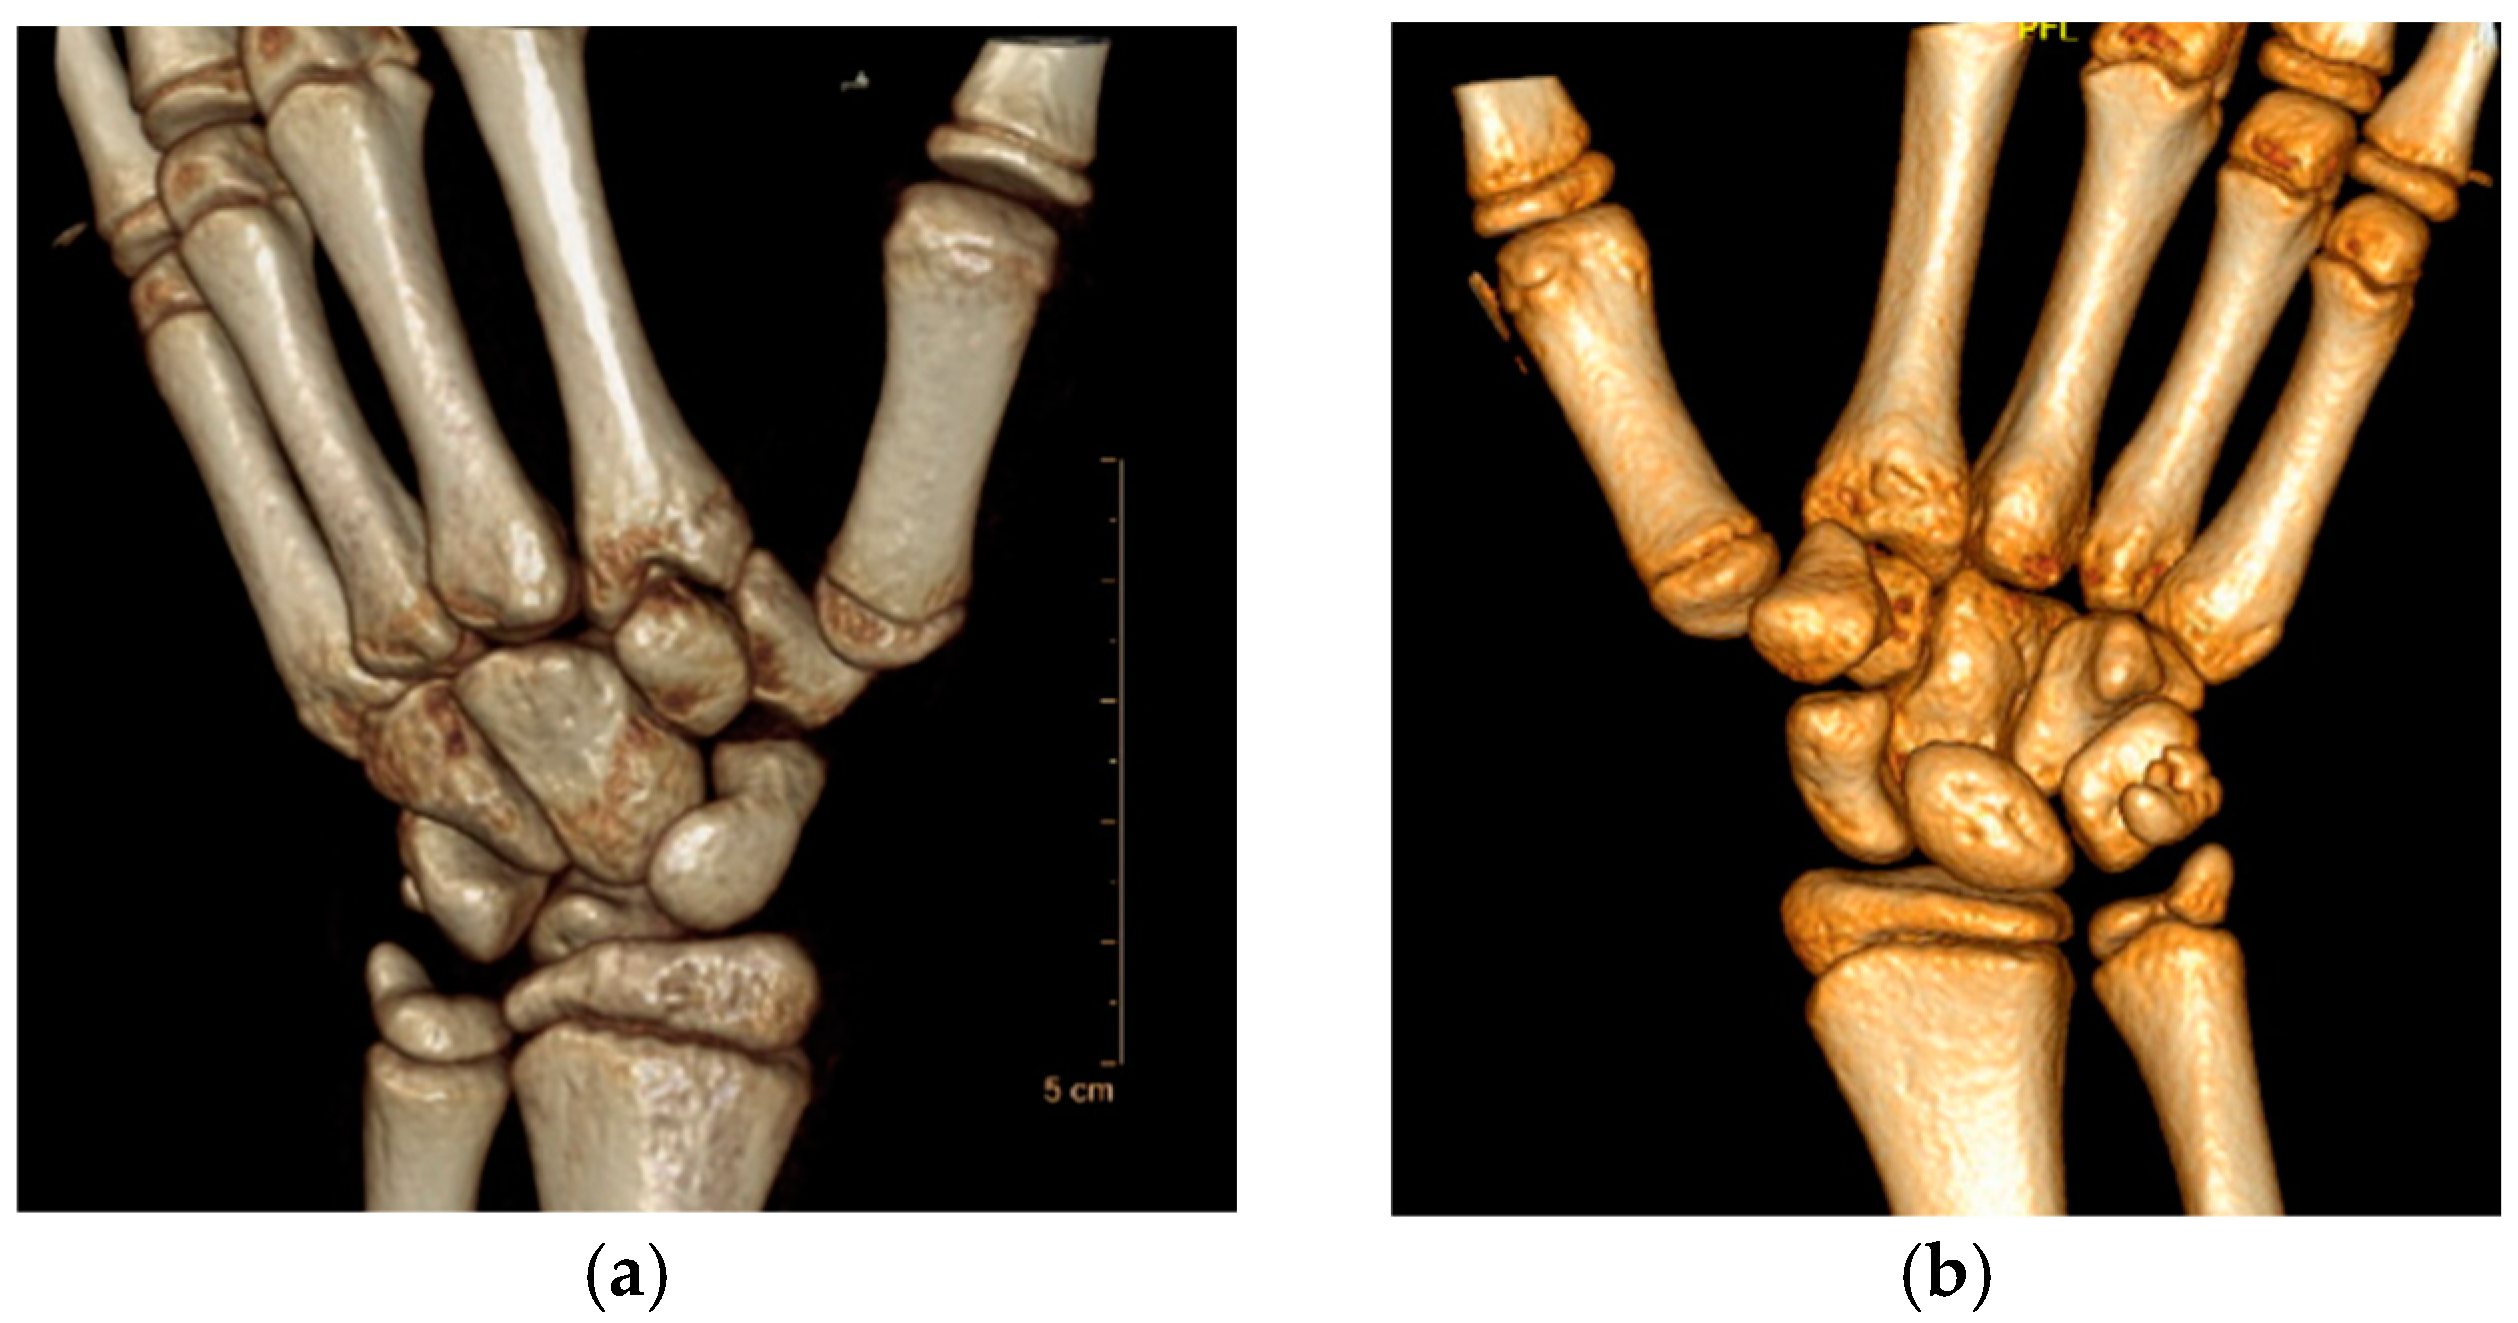

- Roberts projection—strict AP view of the TMC joint. Roberts proposed forced pronation of the wrist and forearm to compensate for the obliquity of the longitudinal axis of the TMC joint in relation to the anatomical axis of the hand. This projection provides a strict profile of the interline of the trapeziometacarpal and scaphotrapezial joints and allows better visualization of the trapezium without carpal superimposition [21] (Figure 2a).